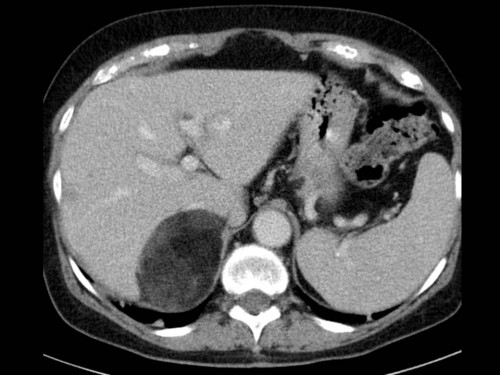

Zufallsbefund in der Bildgebung

Fall-ID: 75

ICD: D17.9

Sie sind Radiologe in einer Universitätskliniik und erhalten folgende Bildgebung mit einem Zufallsbefund.